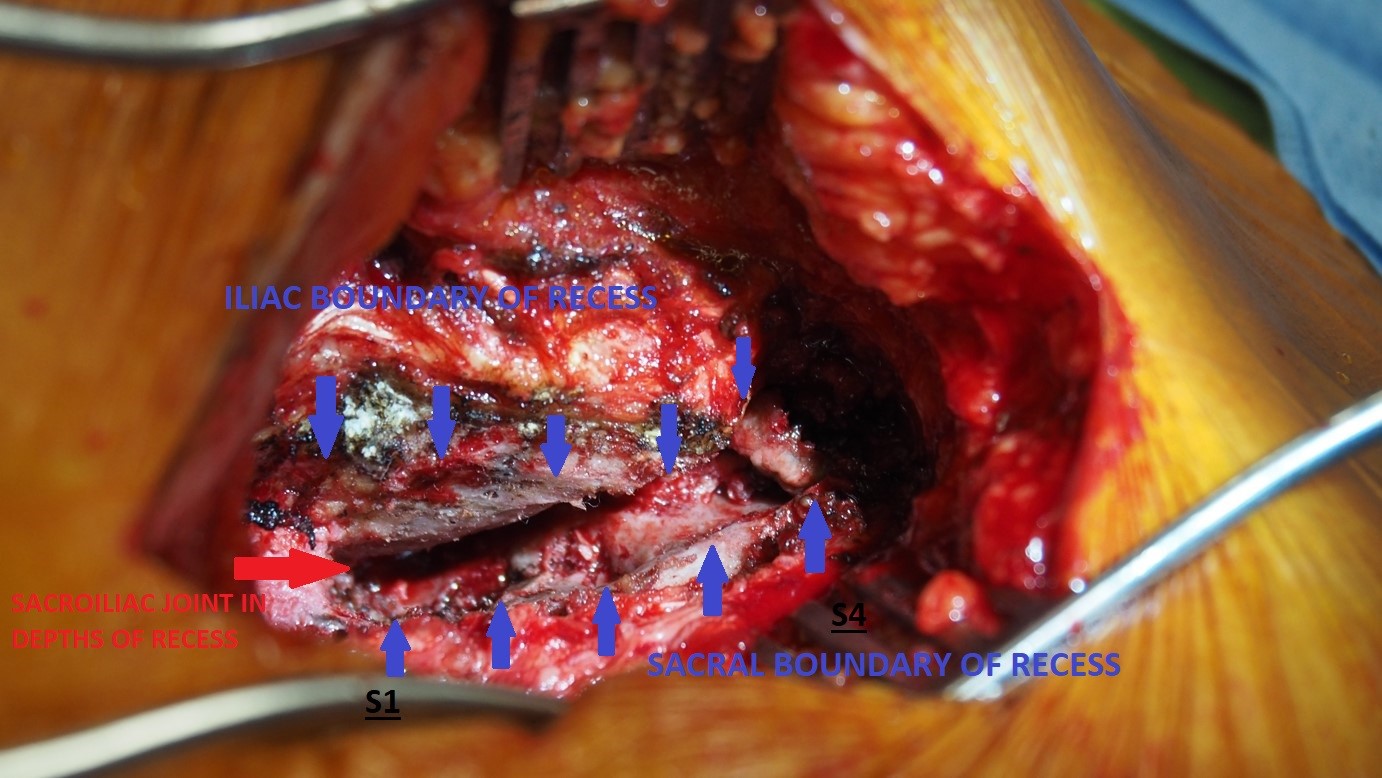

Although the primary goal of the DIANA procedure is stabilisation of the sacroiliac joint, 90% of the procedure itself is actually performed in a large space behind the sacroiliac joint called the sacral recess.

1. Complete exposure of the sacral recess – via a paramedian muscle-splitting incision. The recess is then emptied of soft tissue along this entire extent.

2 & 3. Distraction and fixation of the sacroiliac joint –the sacroiliac joint is indirectly distracted by distracting the medial (sacral) and lateral (iliac) boundaries of the sacral recess. To achieve this a guide pin is implanted using fluoroscopic control into the iliac bone of the pelvis. Positioning and trajectory of the guide pin is an essential component of the procedure and requires careful interpretation of fluoroscopic images performed in the antero-posterior (forward-backward), lateral and oblique planes.

Once the guide pin is positioned correctly and confirmed on the 3 fluoroscopic views, the sacral recess is progressively distracted using a series of progressively larger helical instruments until an appropriate degree of distraction of both the sacral recess and indirectly the underlying sacroiliac joint is achieved.

Once a satisfactory degree of distraction of the sacroiliac joint has been achieved, fixation of the distraction must then be obtained. This is achieved by implanting a DIANA screw sized to match the distraction obtained with the helical instruments.

4. Sacroiliac joint fusion – once the sacroiliac joint has been distracted and fixation of the distraction has been obtained by positioning of the DIANA screw, the exposed sacral recess and sacroiliac joint is then packed with bone graft. This component of the procedure is the most essential element of the whole surgery. The progressive development of a solid consolidated fusion mass within the sacral recess over the 6-9 month period after the surgical procedure maintains the distraction/fixation of the sacroiliac joint achieved with implantation of the DIANA screw and painful of the degenerative sacroiliac joint.